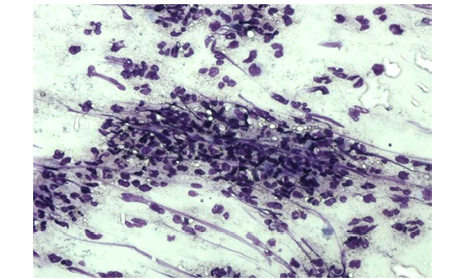

Группа сравнения (3–5 сутки). Препарат представлен в основном клеточно-тканевым детритом и большим количеством экссудата, включающего группы кокковых микроорганизмов. Нейтрофильные лейкоциты с признаками дегенерации и цитолиза (рисунок 2).

Рисунок 2. Мазок – отпечаток ожоговой раны пациента группы сравнения, 4-е сутки. Признаки микробной контаминации раны. Дегенеративные изменения и цитолиз нейтрофильных лейкоцитов, единичные макрофаги. Окраска азур-эозином по Романовскому (х100).

Figure 2. Touch smears of the burn wound of the patient of the control group, day 4. Signs of microbial contamination of the wound. Degenerative changes and cytolysis of neutrophilic leukocytes, single macrophages. Azur-eosin staining according to Romanovsky (x100).